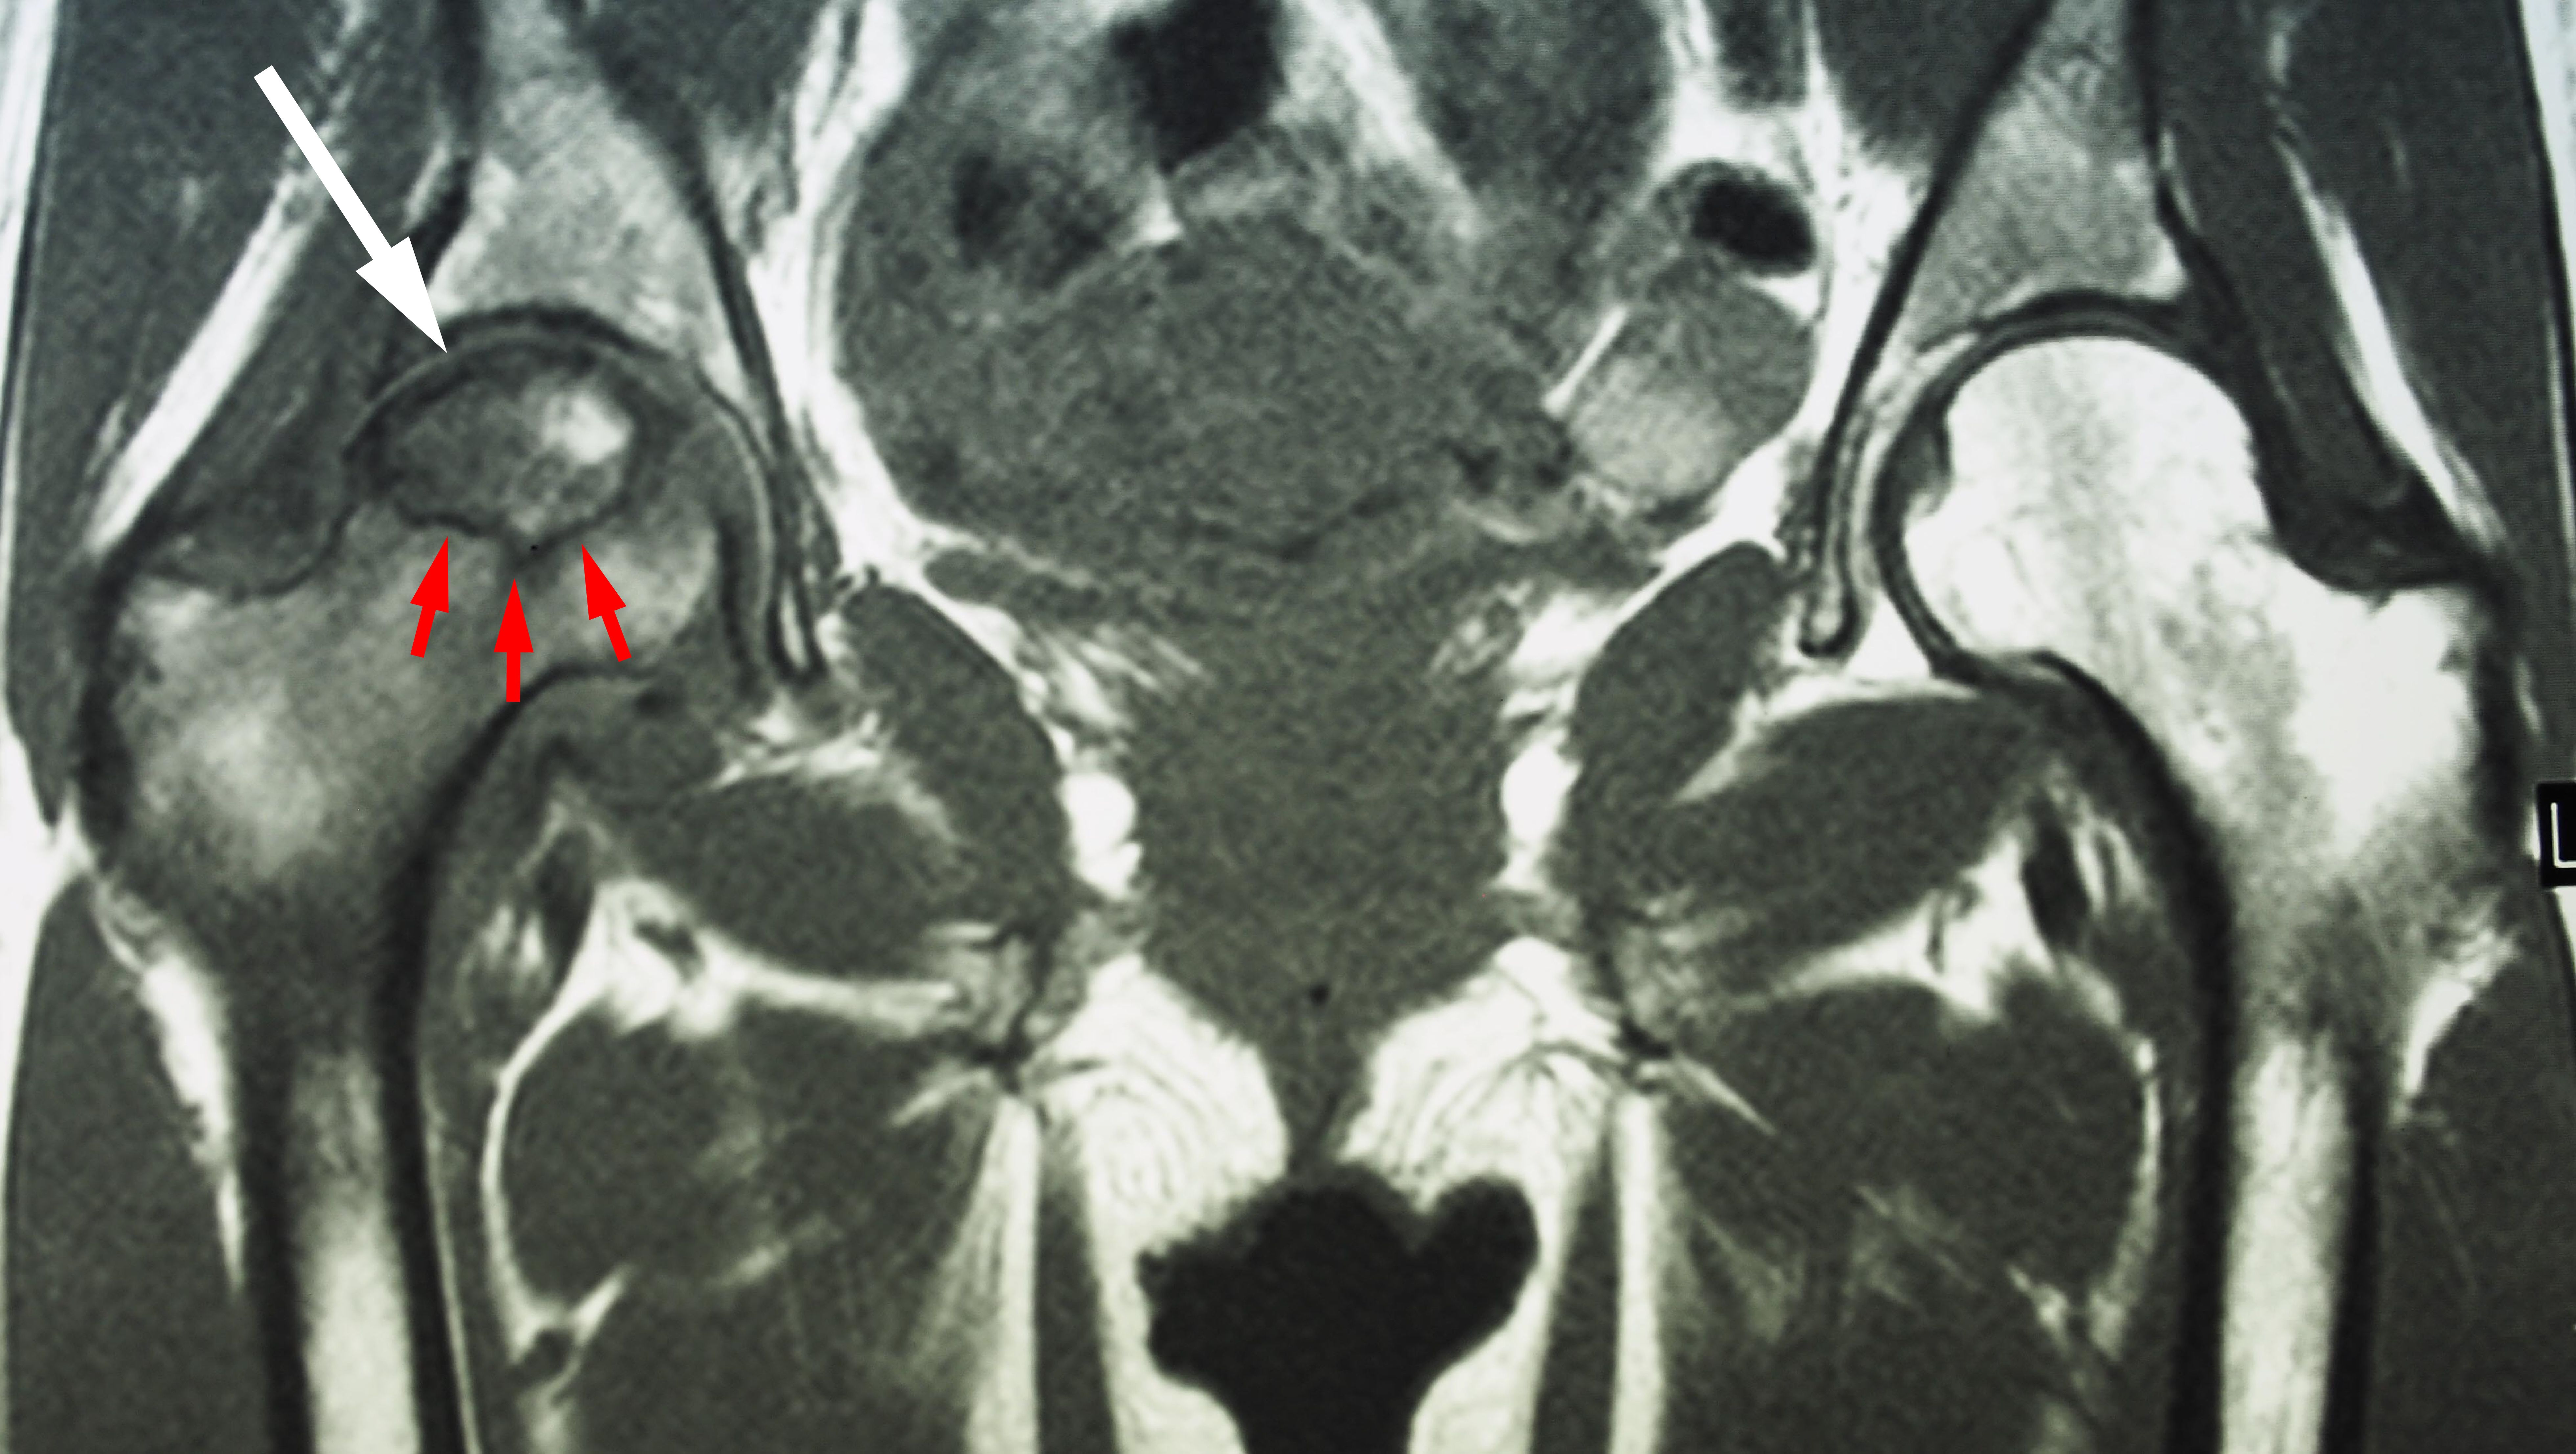

A Case Of Bilateral Bursitis Of The Hip Joints Eurorad